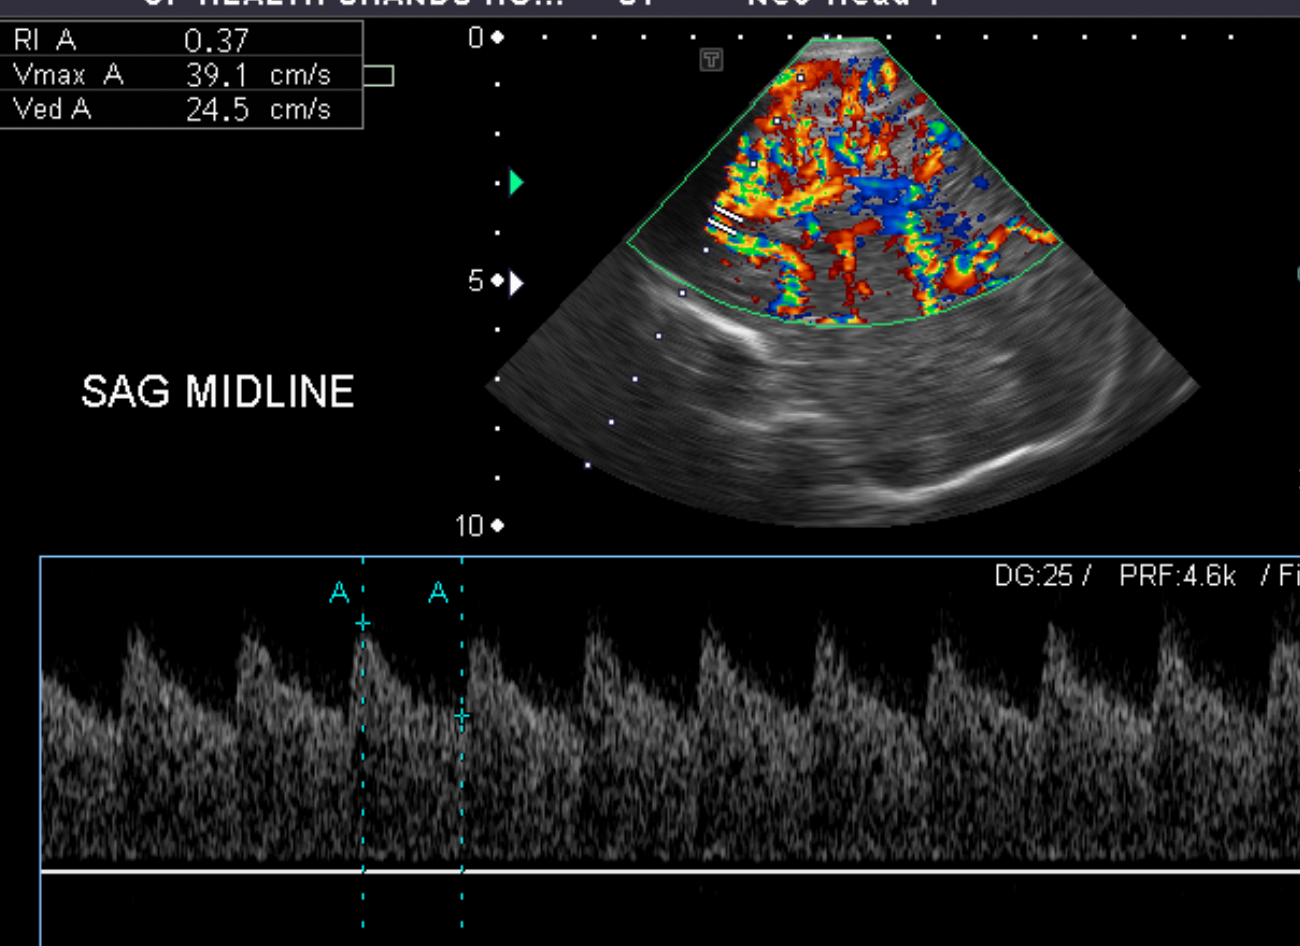

On color Doppler examination, the Resistive index in the anterior cerebral artery is…

There is a loss of the diastolic flow on the Doppler exam. [Yes/No]

There is altered vascularity on Doppler imaging. [Yes/No]